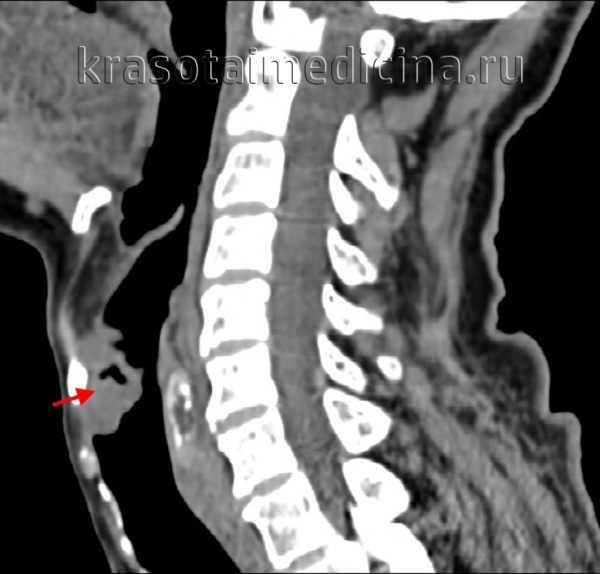

- Компьютерная томография (КТ) дает возможность определить размеры опухоли и ее распространение по лимфатическим узлам и окружающим тканям;

Дополнительными методами в диагностике рака гортани являются исследования голосовой функции, позволяющие оценить подвижность голосовых связок, форму голосовой щели и пр. К ним относятся стробоскопия, электроглоттография, фонетография. Распространенность рака гортани оценивают при помощи рентгенографии и МСКТ гортани. Наличие метастазов в ткани шеи выявляют при помощи УЗИ. Для определения регионарного метастазирования производят биопсию лимфатического узла.

При постановке диагноза учитывают результаты КТ и МРТ гортаноглотки и УЗИ шеи. Решающую роль в выявлении рака гортаноглотки играют данные фиброфаринголарингоскопии. При проведении исследования специалист осуществляет визуальную оценку размера, локализации и структуры новообразования, а затем выполняет биопсию подозрительного участка. Окончательный диагноз выставляют онкологи на основании гистологического исследования.